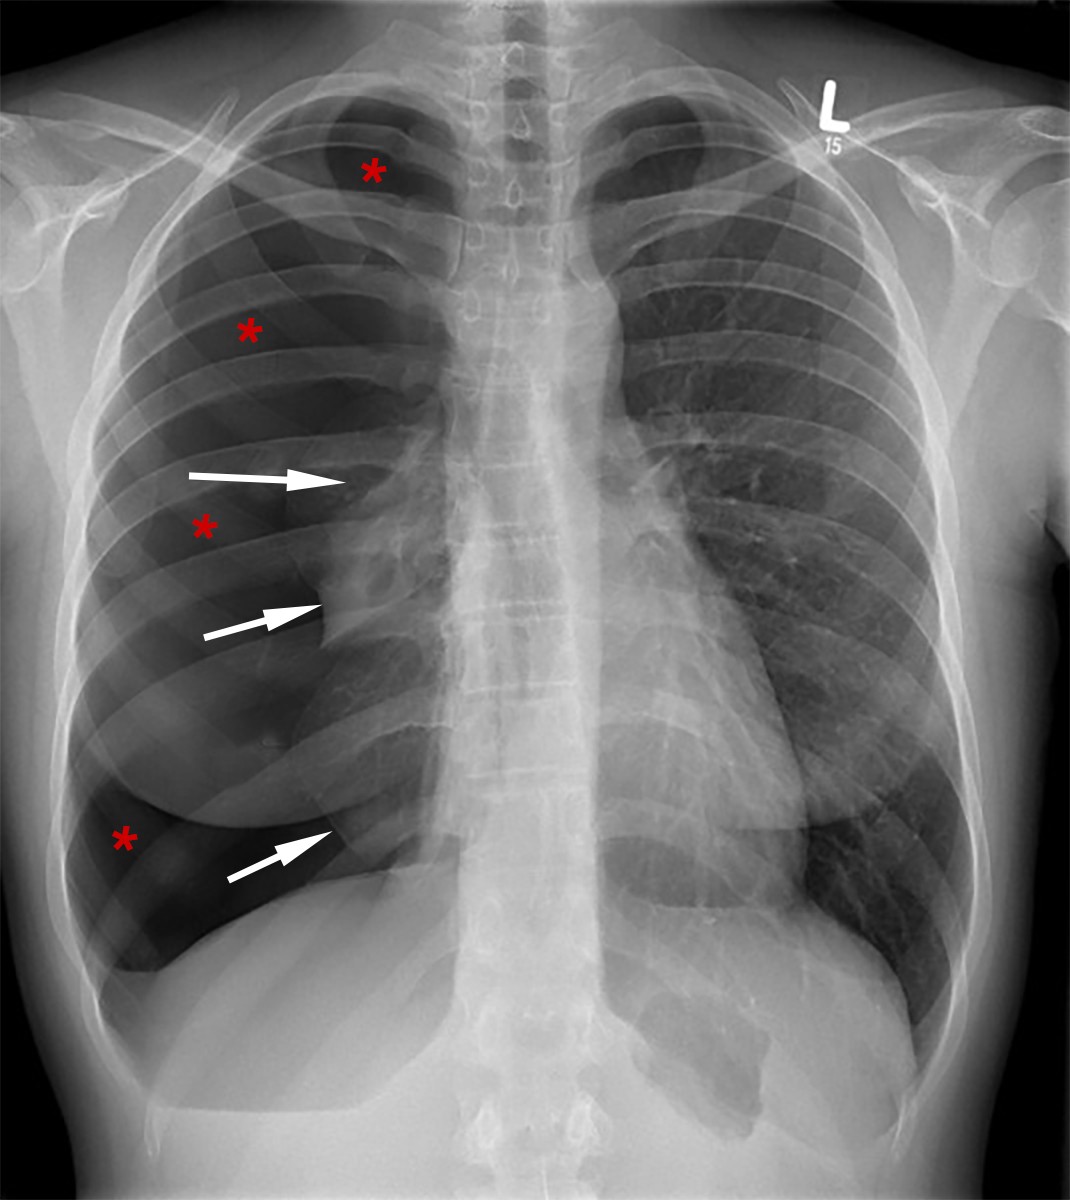

| Abb. 6 |

| Verdickung der Wand des linken Ventrikels mit unnatürlich hohen R-Zacken (rote Pfeile) und Senkungen der ST-T-Strecke (schwarze Pfeile) bei Herzmuskelkrankheit |

Im Röntgenbild des Brustkorbes kann man u.U. Hinweise auf eine Erkrankung des Herzens sehen, wie z.B. Vergrößerungen und Verdickungen des linken Ventrikels, jedoch sind diese Röntgenhinweise im allgemeinen nicht sehr aussagekräftig.

Das Röntgenbild ist aber dennoch wichtig, denn es zeigt auch Erkrankungen der Lungen, wie z.B. einen Pneumothorax (Luftansammlung im Spalt zwischen Lungen- und Brustfell), bei dem ein Teil der Lungen zusammenfällt (Abb. 6).

U.U. kann man aber auch die Zeichen einer Lungenentzündung, einer Flüssigkeitsansammlung im Brustkorb (Pleuraerguß) oder auch Tumore sehen.